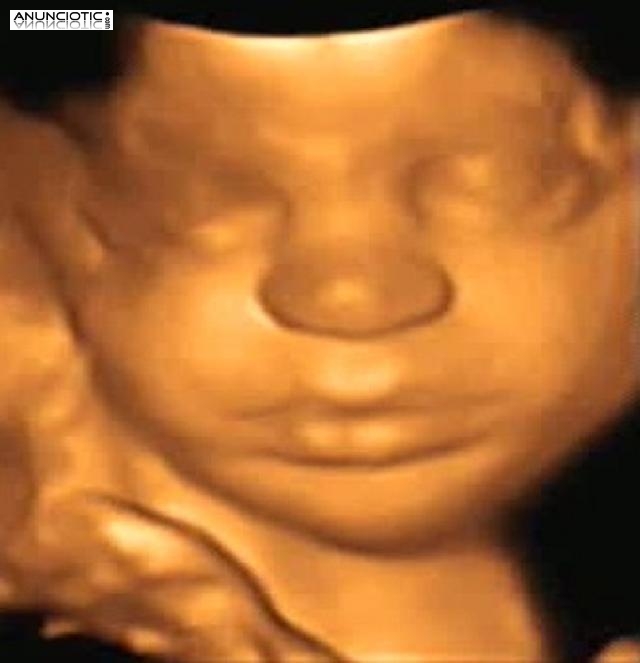

Ecomamá es un centro de imagen 4d prenatal cuyo objetivo es dar a conocer al bebé antes de su nacimiento. Esta maravillosa experiencia permite adentrarnos al pequeño mundo en el que vive el bebé. Gracias a ello se pueden ver gestos faciales nunca vistos como el bostezo, una sonrisa, el parpadeo o la succión. Todo ello en un ambiente cálido relajado y con todas las comodidades.

Un regalo para tu bebé a través de nuestra tecnología 4d prenatal.

¡Detén sus momentos inolvidables!